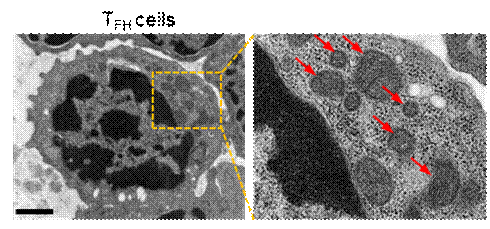

图2. 透射电镜下看到TFH细胞内皱缩和损伤的线粒体,显出铁死亡特征 (图片来源于Nature Immunology) |